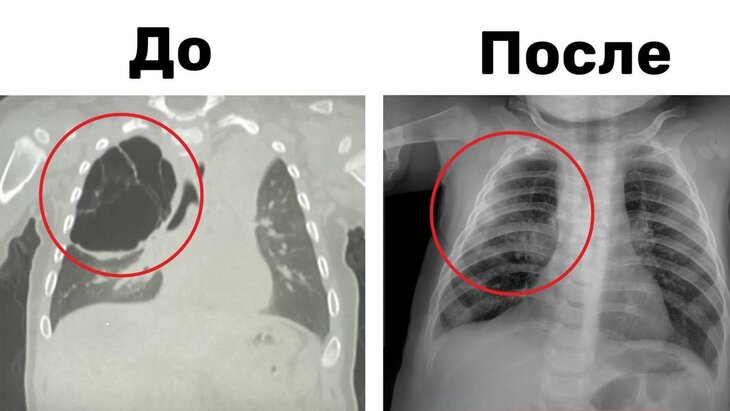

В Подмосковье ребенку удалили 15-сантиметровую кисту легкого

М. Рошаля, провели операцию по удалению 15-сантиметровой кисты легкого у восьмимесячного младенца. Об этом сообщили на официальном сайте министерства здравоохранения Московской области. Кистозное образование было обнаружено во время воспалительного процесса, вызванного ОРВИ, и оказывало давление на здоровую ткань легкого, мешая его нормальному развитию. Никита Степаненко, заведующий отделением детской хирургии № 2, отметил, что у ребенка был ранее не выявленный дефект легкого - кистозная мальформация, что привело к образованию кист и развитию воспалительного процесса. Операция, проведенная торакоскопическим методом, позволила удалить кисту вместе с пораженной частью верхней доли правого легкого без необходимости крупного разреза. Врачи отметили успешное проведение операции, которая длилась около часа. В настоящее время ребенок чувствует себя хорошо и уже выписан домой. В другой новости, известно, что девочке Луне Феннер из США, родившейся с "маской Бэтмена", проведут две операции на лице в Санкт-Петербурге. Первая операция состоялась 7 мая, а вторая запланирована на июль. Луна Феннер появилась на свет с гигантским черным родимым пятном (меланоцитарным невусом) в 2019 году. Благодаря сбору средств через благотворительность и привлечению внимания СМИ, к этой истории обратил внимание краснодарский хирург-онколог Павел Попов, который предложил помочь девочке в России.